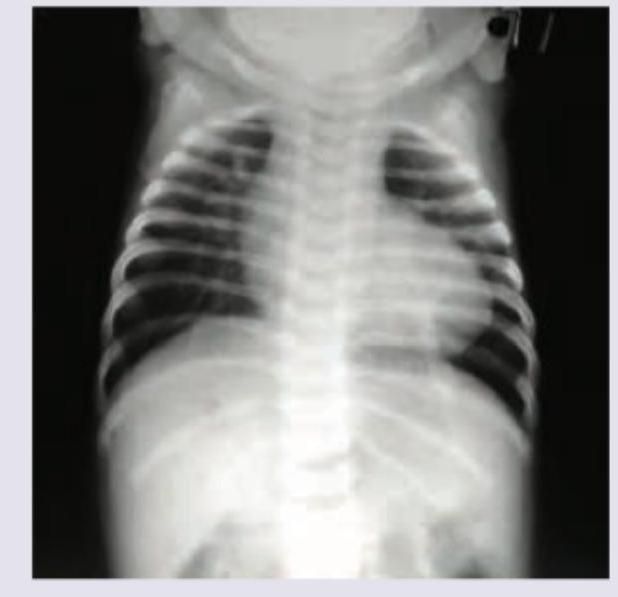

One-month-old child with tet spells. Incorrect about the image shown?

Explanation: ***Pulmonary oligaemia*** - This is the **INCORRECT** statement about the image shown. - The chest X-ray demonstrates **increased pulmonary vascular markings** (pulmonary plethora), not oligaemia. - While **Tetralogy of Fallot** classically presents with **pulmonary oligaemia** due to right ventricular outflow tract obstruction, this particular image shows **increased pulmonary blood flow**, which is atypical and may suggest associated findings or a different physiology. - **Pulmonary oligaemia** would show decreased vascular markings with clear, dark lung fields, which is not seen in this image. *Increased CT ratio* - The **cardiothoracic (CT) ratio** is within normal limits or mildly increased for an infant. - In Tetralogy of Fallot, the heart size is typically **normal to mildly enlarged**, which is consistent with this image. - This statement is **CORRECT** about the image. *Right sided aortic arch* - A **right-sided aortic arch** can be identified in this image, with the aortic knob positioned on the right side of the trachea. - This finding is present in approximately **15-25% of patients with Tetralogy of Fallot** and is a classic associated anomaly. - This statement is **CORRECT** about the image. *Coeur en sabot* - The cardiac silhouette demonstrates the classic **"boot-shaped heart"** (coeur en sabot) appearance. - Characteristic features include an **upturned cardiac apex**, **concave pulmonary artery segment**, and **right ventricular hypertrophy**. - This morphology results from **pulmonary artery hypoplasia** and **right ventricular hypertrophy**, both hallmarks of Tetralogy of Fallot. - This statement is **CORRECT** about the image.